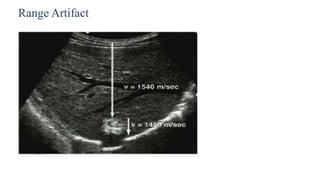

Range Artifact